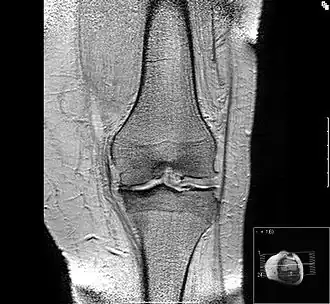

Исход артроза — полное разрушение сустава с формированием анкилоза — полной неподвижности сустава или неоартроза с неестественной подвижностью. Это сопровождается тяжёлым нарушением функции конечности. В последнее время, не дожидаясь исхода заболевания, всё чаще применяют специальные операции по замене сустава протезом — эндопротезирование сустава. На рисунке изображена типичная для терминальной стадии артроза коленного сустава варусная деформация колена в сочетании с боковой патологической нестабильностью коленного сустава. Артроз блоковидного или шаровидного сустава, такого как тазобедренный, завершается анкилозированием. При этом замыкание сустава обычно происходит в нефизиологическом (порочном) положении конечности. В данном случае мы видим бедро в положении сгибания и приведения, при котором нога укорачивается, а ось конечности и биомеханика опорно-двигательной системы существенно нарушается.

В настоящее время используется рентгенологическая классификация остеоартроза по Kellgren-Lawrence[18][19]:

- I стадия (сомнительный) — сомнительное сужение суставной щели, возможны остеофиты

- II стадия (мягкий) — определённые остеофиты и сомнительное сужение суставной щели

- III стадия (умеренный) — умеренные остеофиты, определённое сужение суставного пространства, возможная деформация костей

- IV стадия (тяжёлый) — большие остеофиты, сужение суставного пространства, тяжёлый остеосклероз, определённая деформация костей